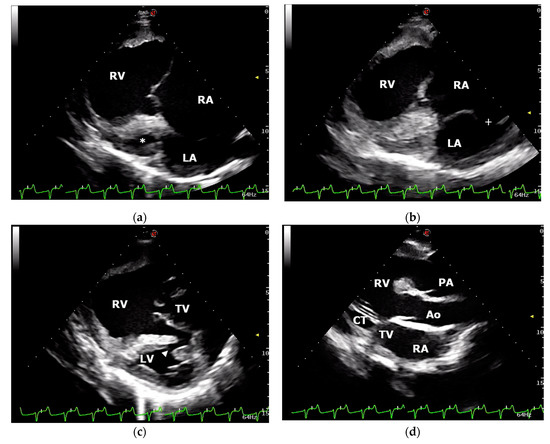

2.1. Case Description and Clinical Investigations